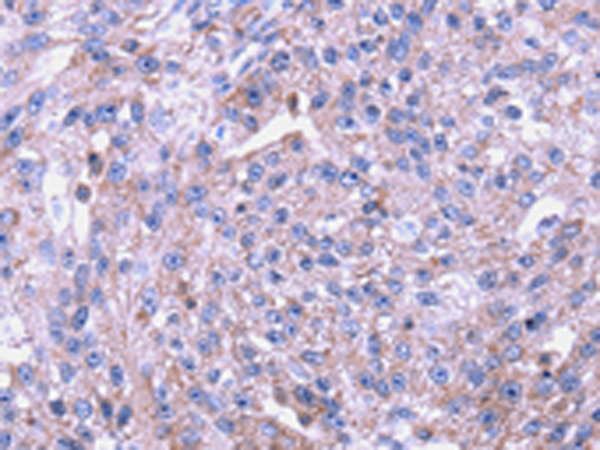

分类: 科研抗体货号: P08776别名: ENT4; PMAT应用: WB,IHC反应种属: Human